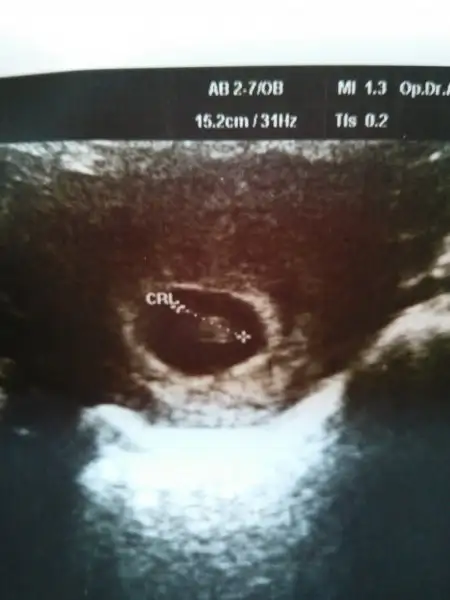

Şimdi kendi usg me tekrar baktım. 6+3 günlük karından. Tekrar bakar mısın canım.Evet canım bende okumuştum zaten bebekle plasentanın farklı yerlerde olduğunu biliyorum. Slvestr arkadaşımız bebek nerdeyse plasentada orda olur demişti. Ama öyle değil. Benim ilk gebeliğimde bariz bebek solda hatta en sola yapışık yani. Ama plasenta sağda ve benim 11 aylık bir cimcimem var. Yani plasenta olayı ilk gebeliğimde tuttu. Şimdi bebekte plasentada solda bakalım sonuç ne olacak. Eğer yine kızım olursa plasenta olayı yalan arkadaşlar. Tutanlar tesadüf dicez napalım

Cnm bu konuda bi karara varabilmemiz için burdaki plasentası sağda veya solda dediğimiz arkadaşlardan bi cvp gelmesi bizimde ona göre işe yarayıp yaramadıgını öğrenmemiz gerekiyo. Fakat çoğu daha cinsiyeti öğrenemedi galiba. Ben öğrenenlerin eski usglerine bakıorm bi kaç tane tuttu yani plasenta ve bebek solda oğlu olcakmş. Ama bi kaç tane tutması istisna olabilir canım. Ben hiçbi teoriye %100 doğru diyemem.Saol cnm yorumun için,bende onu merak ediyordum bebek solda plasenta sağda nasıl oluyor diye.18 haftalıkken gittiğimde kıza benzettim ama alışveriş falan yapma obur ay 3d gircen o zaman net belli olur dedi.netteki plasenta fotolarına baktım bebek nerdeyse plasentada orda benim niye ayrı ayrı ki:)Bide bebegin solda olması mi önemli yoksa plasentanın solda olması mi önemli cnm.

yabancı sitelere baktım canım. bebek ile plasenta daha 6 ya da 7 haftalıkken birbirinden uzak olabiliryormuş. bir kaç foto ekliyorum. bu ultrasonlar vajinal. ( bu arada bu bebişlerde plasenta yönü yani ramzi teorisi tutmuş)Cnm bu konuda bi karara varabilmemiz için burdaki plasentası sağda veya solda dediğimiz arkadaşlardan bi cvp gelmesi bizimde ona göre işe yarayıp yaramadıgını öğrenmemiz gerekiyo. Fakat çoğu daha cinsiyeti öğrenemedi galiba. Ben öğrenenlerin eski usglerine bakıorm bi kaç tane tuttu yani plasenta ve bebek solda oğlu olcakmş. Ama bi kaç tane tutması istisna olabilir canım. Ben hiçbi teoriye %100 doğru diyemem.